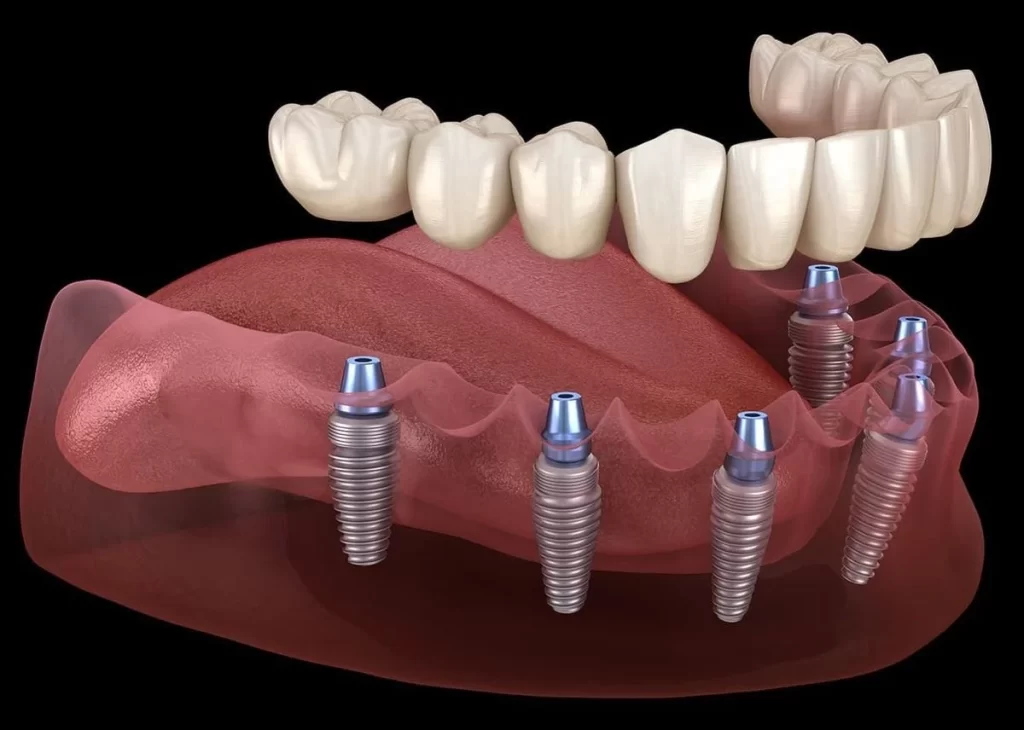

Nadoknade na implantima

Nakon ugradnje implanata, pristupa se izradi kruničnog dela nadoknade, pri čemu se u ustima ne moze zapaziti prisustvo implanta. Visokoestetski zahtevi su postignuti primenom bezmetalne keramike kojom se postize izvanredna estetika i najprirodniji izgled.

U zavisnosti od indikacija i želje pacijenta, nadoknade mogu biti izradjene od keramike koja kao osnovu ima metal ili od visokoestetske bezmetalne keramike kojom se postiže izgled najbliži prirodnom zubu.

Implanti

U savremenoj stomatologiji implanti zauzimaju važno mesto u nadoknadi izgubljenih zuba i vraćanju funkcije žvakanja. Korišćenjem najkvalitetnijih implanata u stomatologiji, stomatološka ordinacija Kocić obezbedjuje vrhunske rezultate u protetskoj rehabilitaciji usne duplje.

Uz primenu najsavremenije opreme i adekvatnih lokalnih anestetika, bezbolan rad je zagarantovan, uz optimalno vreme oporavka.